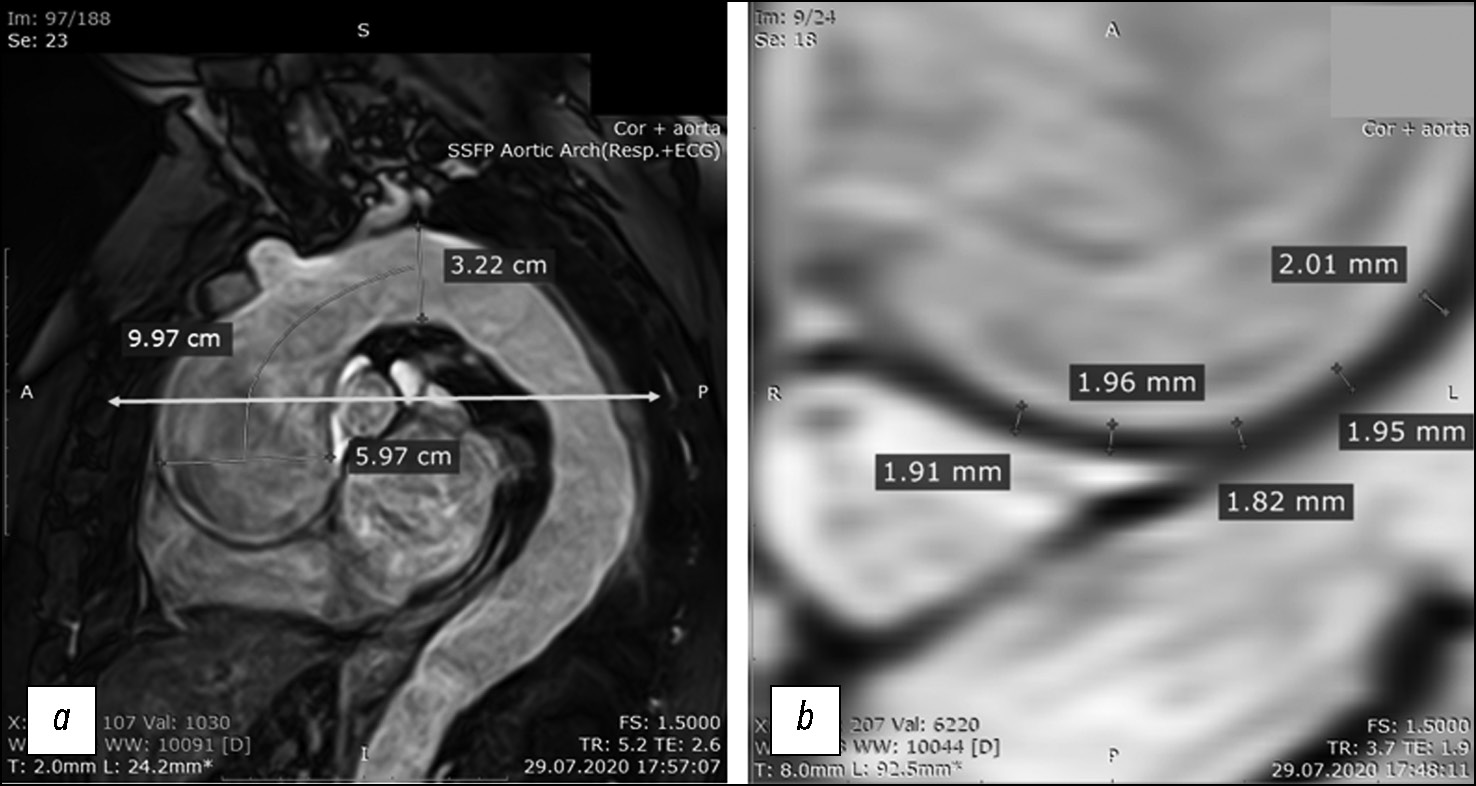

Following cardiac MRI, the patient underwent MRI of the ascending aorta with ECG gating, at the level of crossover with the pulmonary artery bifurcation level, in axial plane, in the cine mode (24 cine frames per cardiac cycle), with the assessment of changes in the aortic wall thickness during a cardiac cycle (Fig. 2b) and diameter and cross-sectional area of the lumen at the study level (marked with an arrow in Fig. 2a). The cardiac MRI findings were processed using a standard method; the left ventricular end-diastolic volume, left ventricular end-systolic volume, and left ventricular ejection fraction were calculated. Moreover, biomechanical parameters of aortic distensibility were obtained based on non-contrast-enhanced cine mode MRI findings.

Fig. 2. Magnetic resonance imaging with ECG gating in patient B-k: (a) magnetic resonance angiography of the thoracic aorta. The lumen at the supravalvular and aortic arch levels and the distances between them, which are used to calculate the ascending aorta volume during systole and diastole and the systolic expansion volume, are shown. The turquoise horizontal line with arrows at the ends represents the tomographic slice level; (b) transverse tomographic slice of the ascending aorta in the wall area, with thickness measurements for the subsequent calculations of Young’s modulus parameters. The measurements are marked by thin green lines, with respective values.